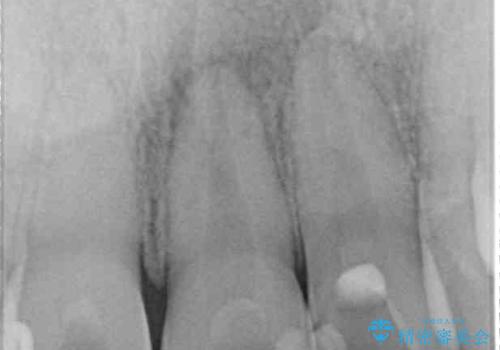

変色が気になっていたものの痛みがなかったので看過していましたが、歯肉が腫れることが頻回となったため来院されました。

歯髄は既に壊死していたため、根管治療を行い、その後オールセラミッククラウンにて補綴することとしました。